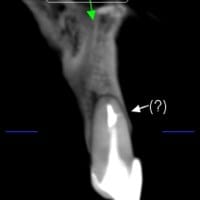

Fisura tratamiento conducto por corte transversal

Quisiera saber si una fisura en tratamiento de conducto, visto por corte transversal, ¿Es causal de extracción?